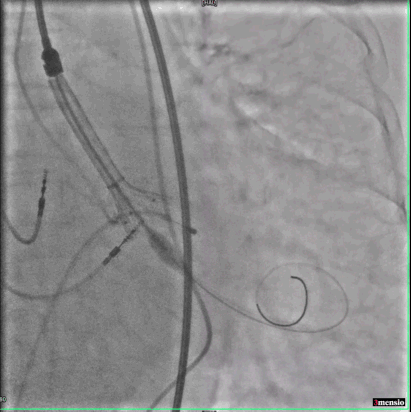

跨瓣